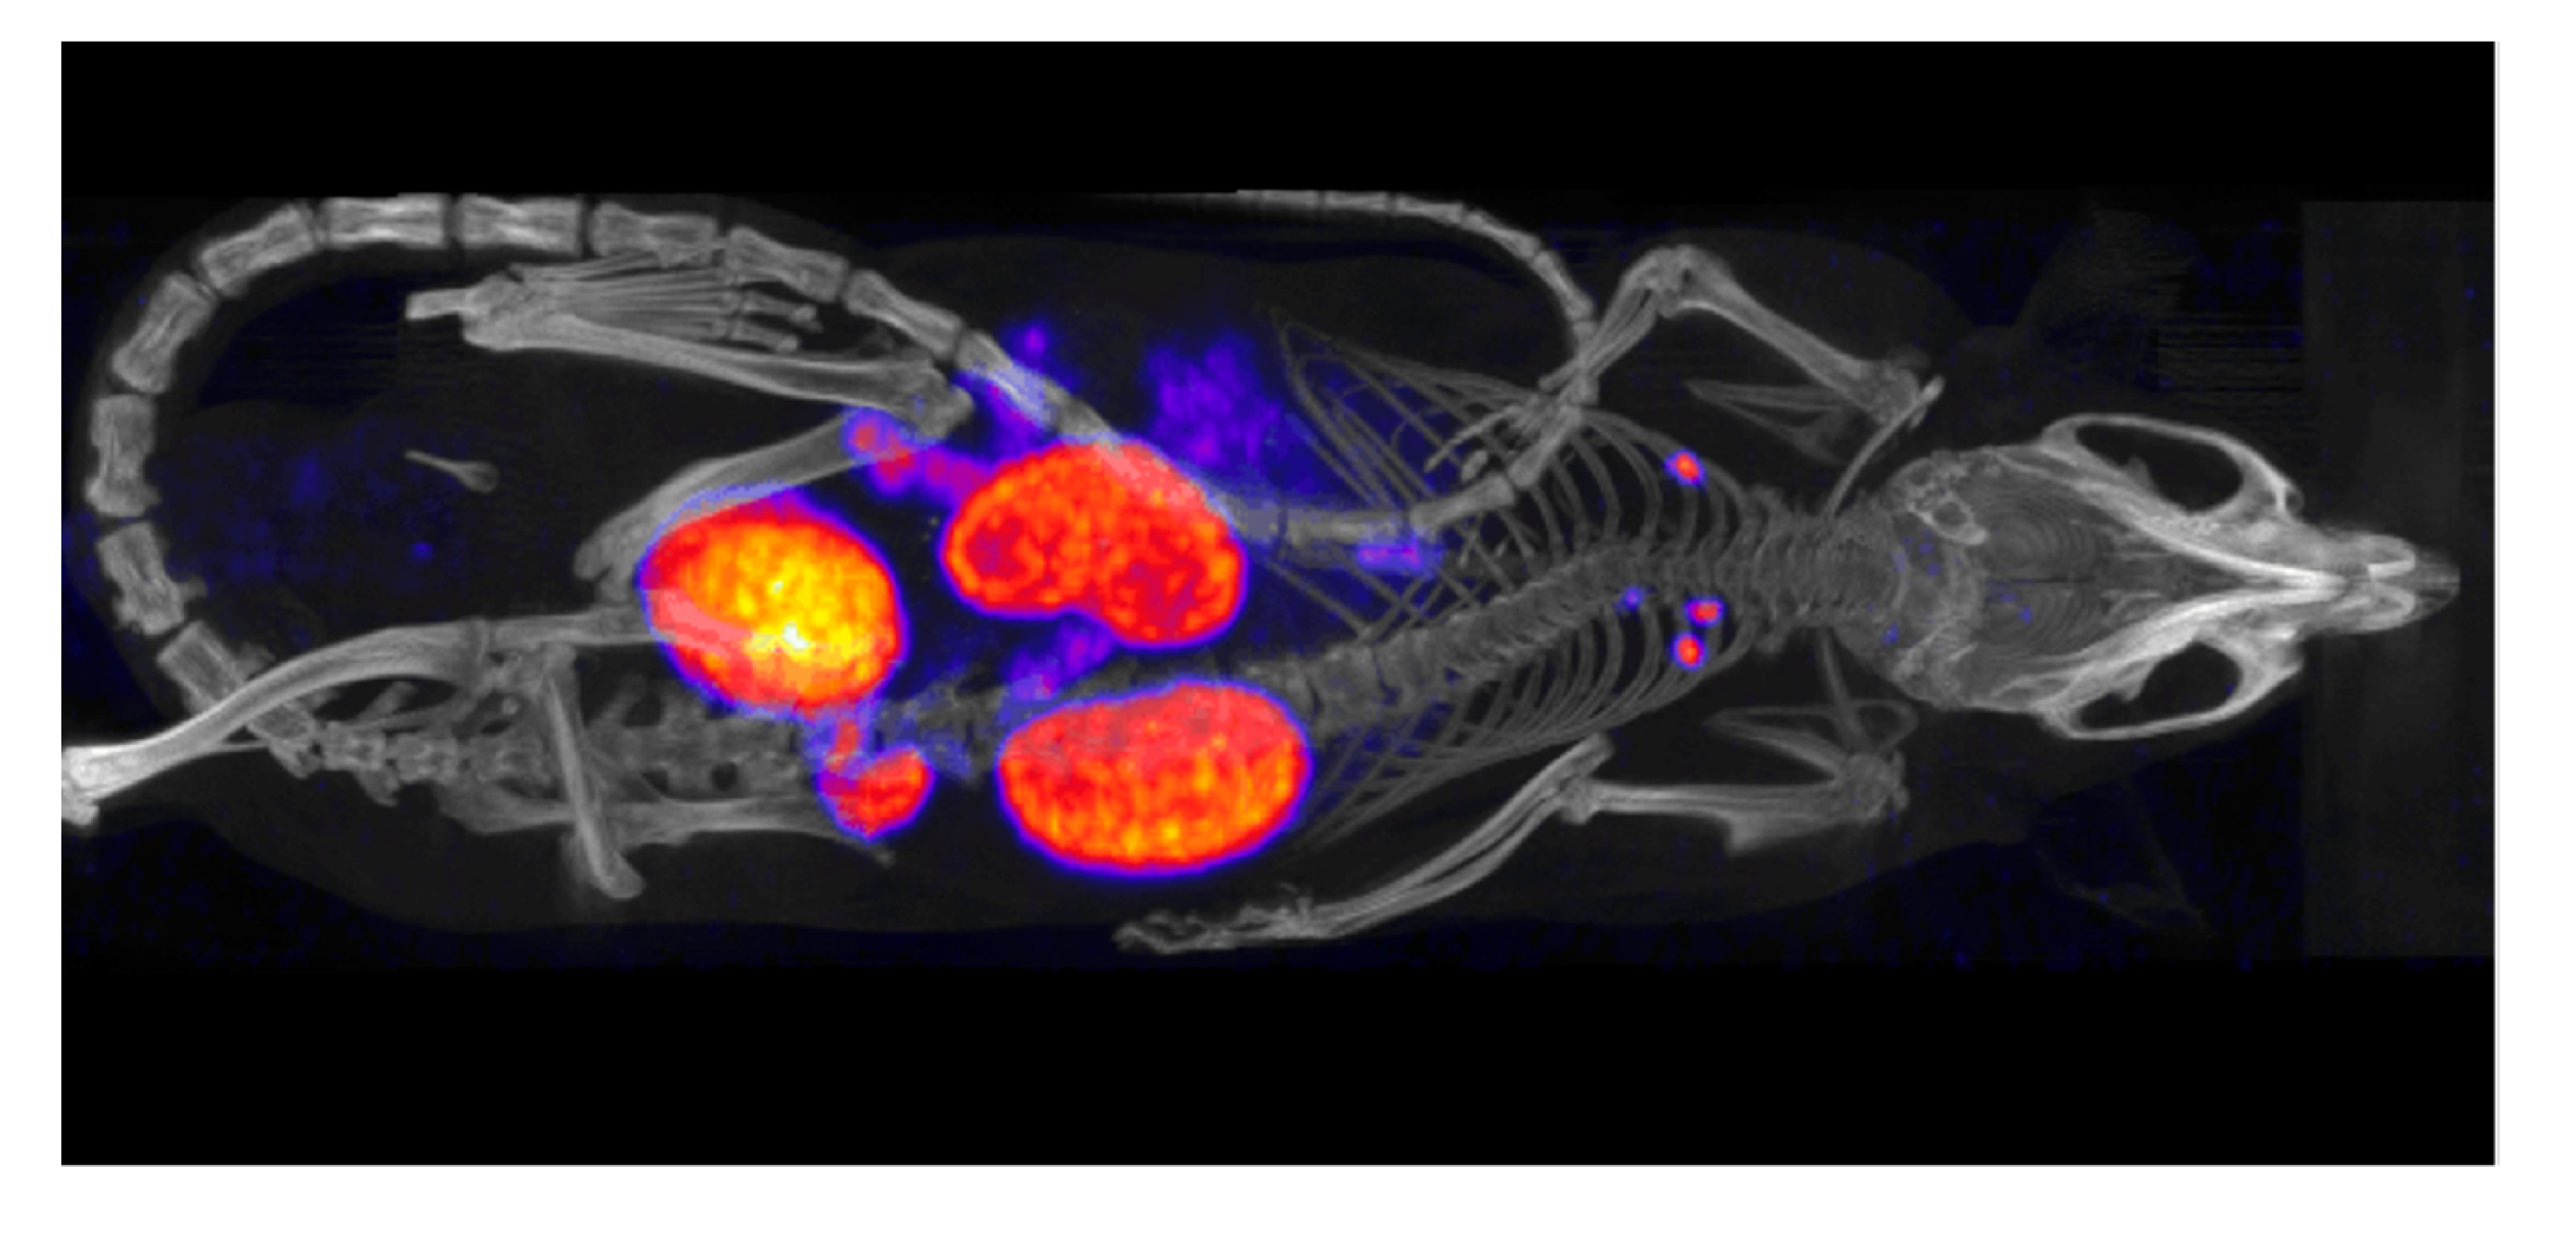

4. Physical Factors that Affect the Activity Measurement

12. Pre-Clinical Dosimetry with μSPECT/μCT and μPET/μCT